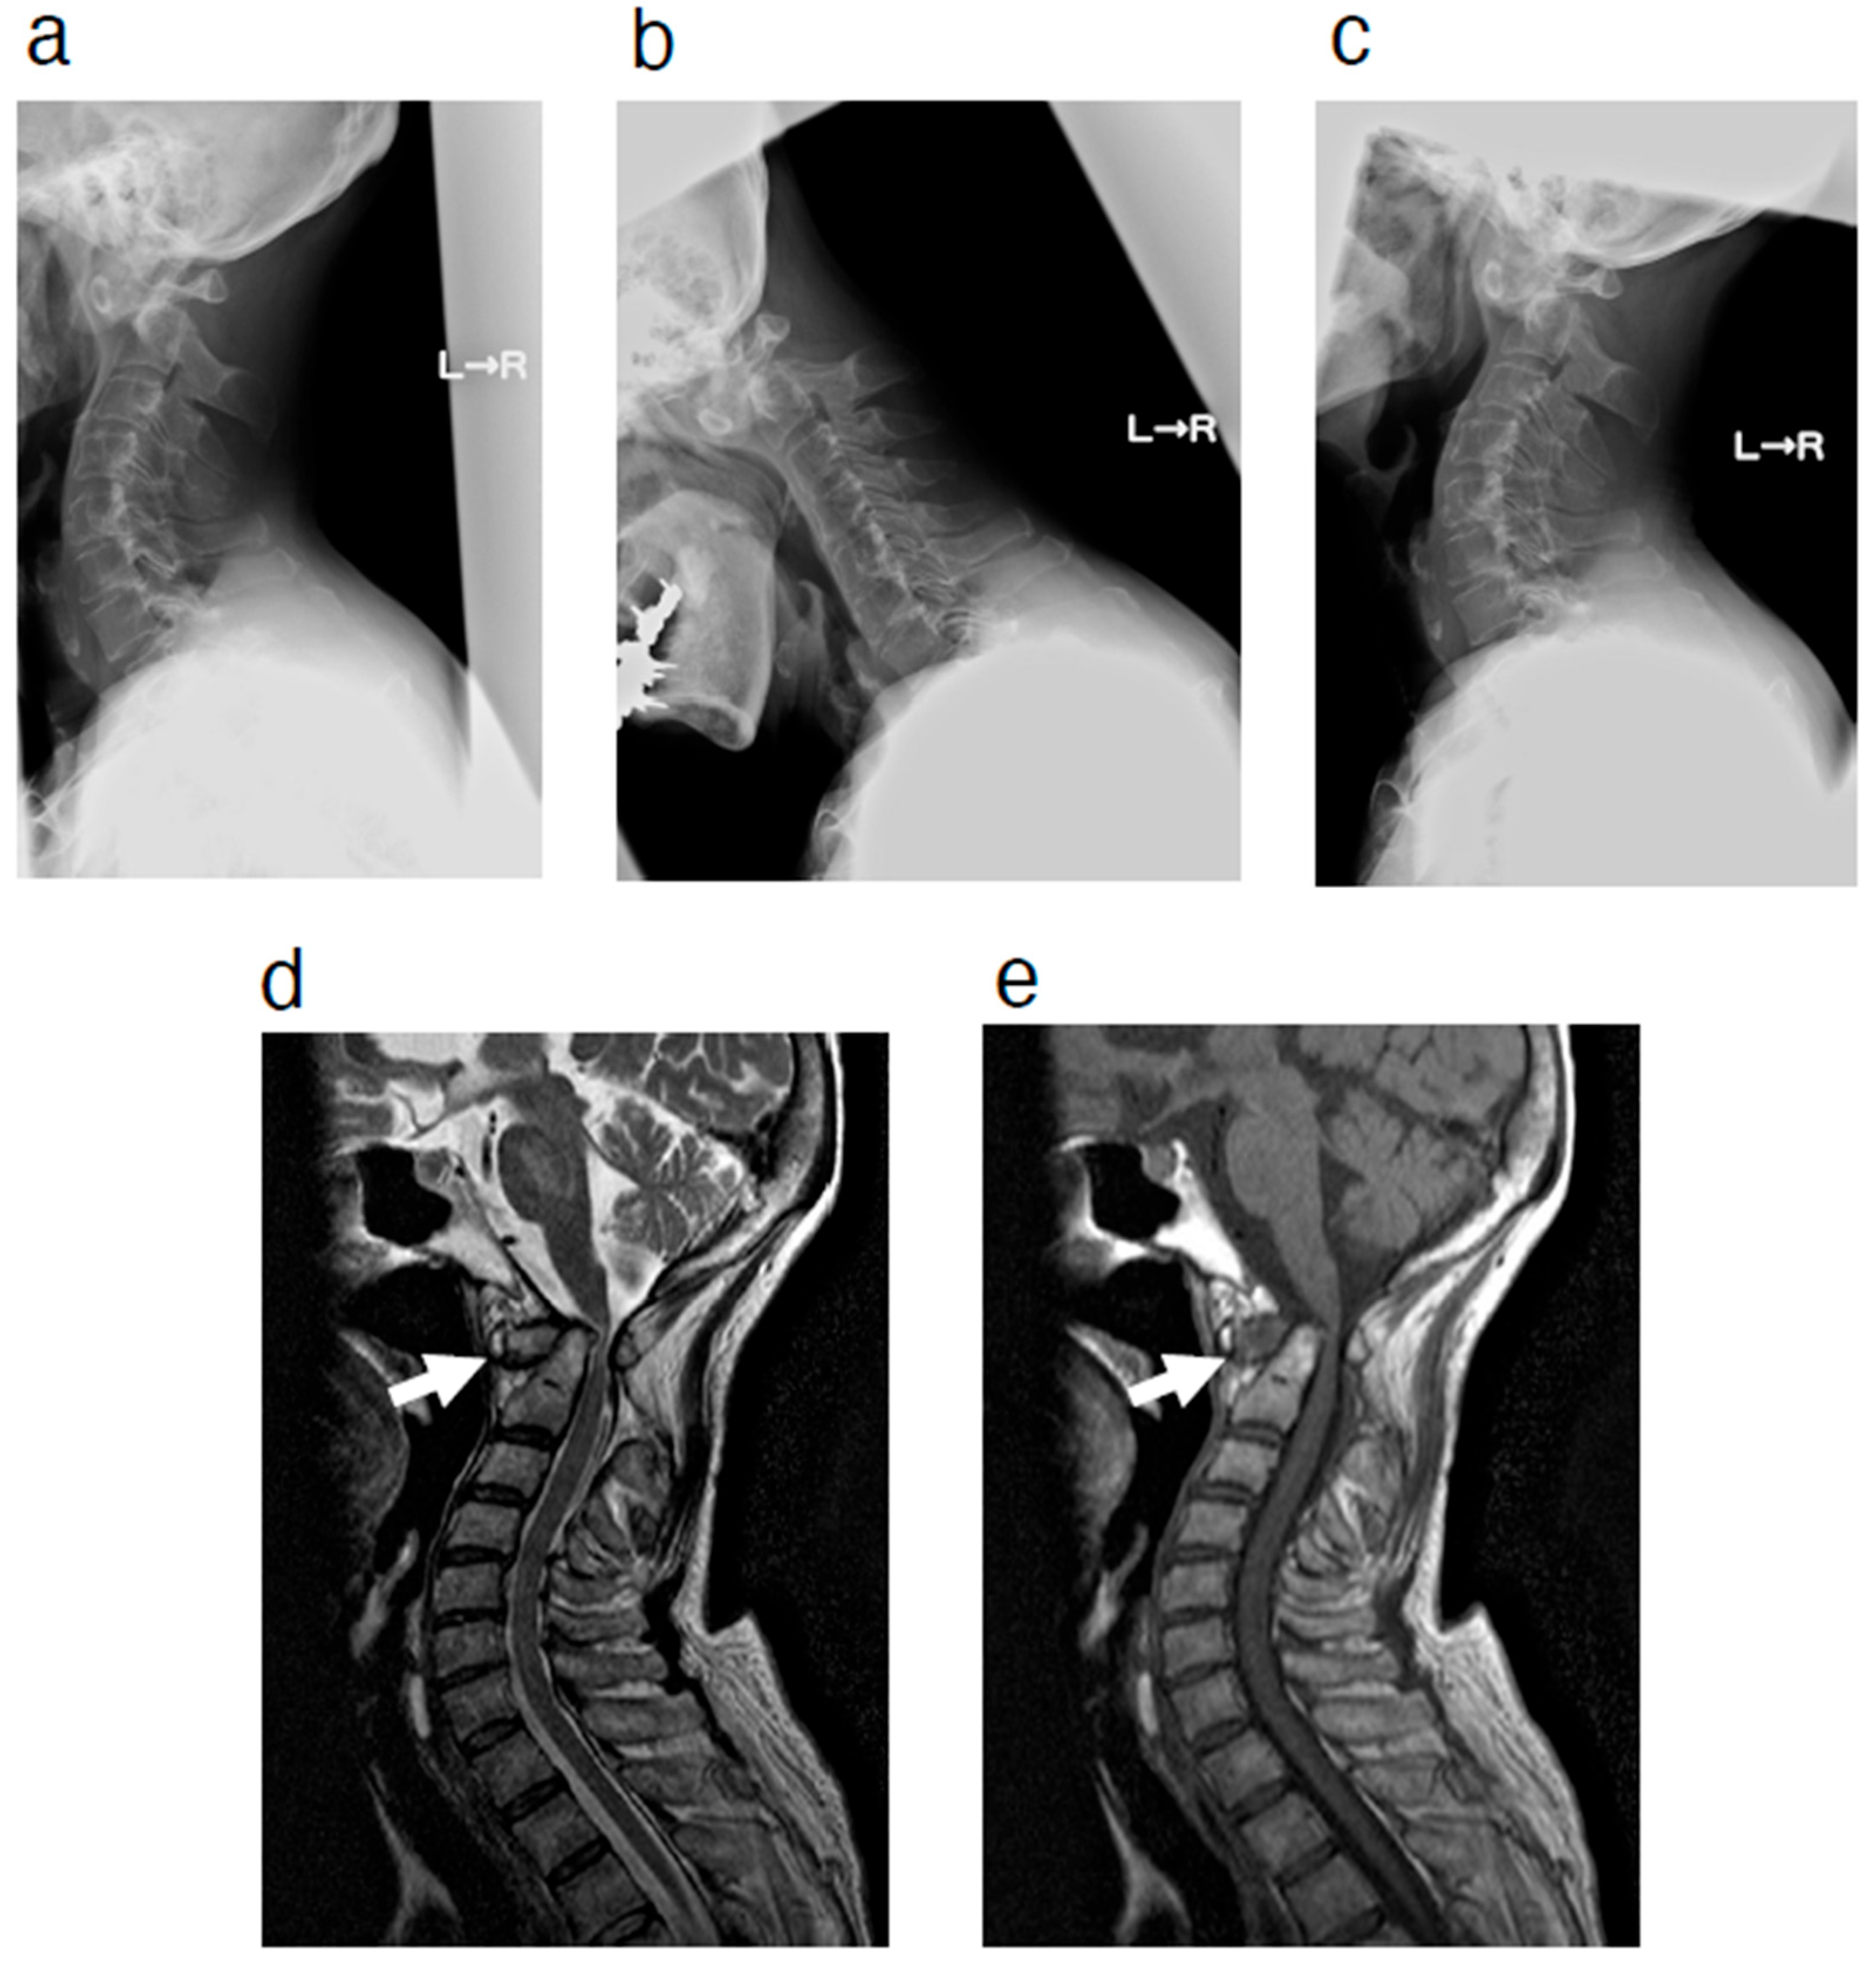

2. Case Presentation